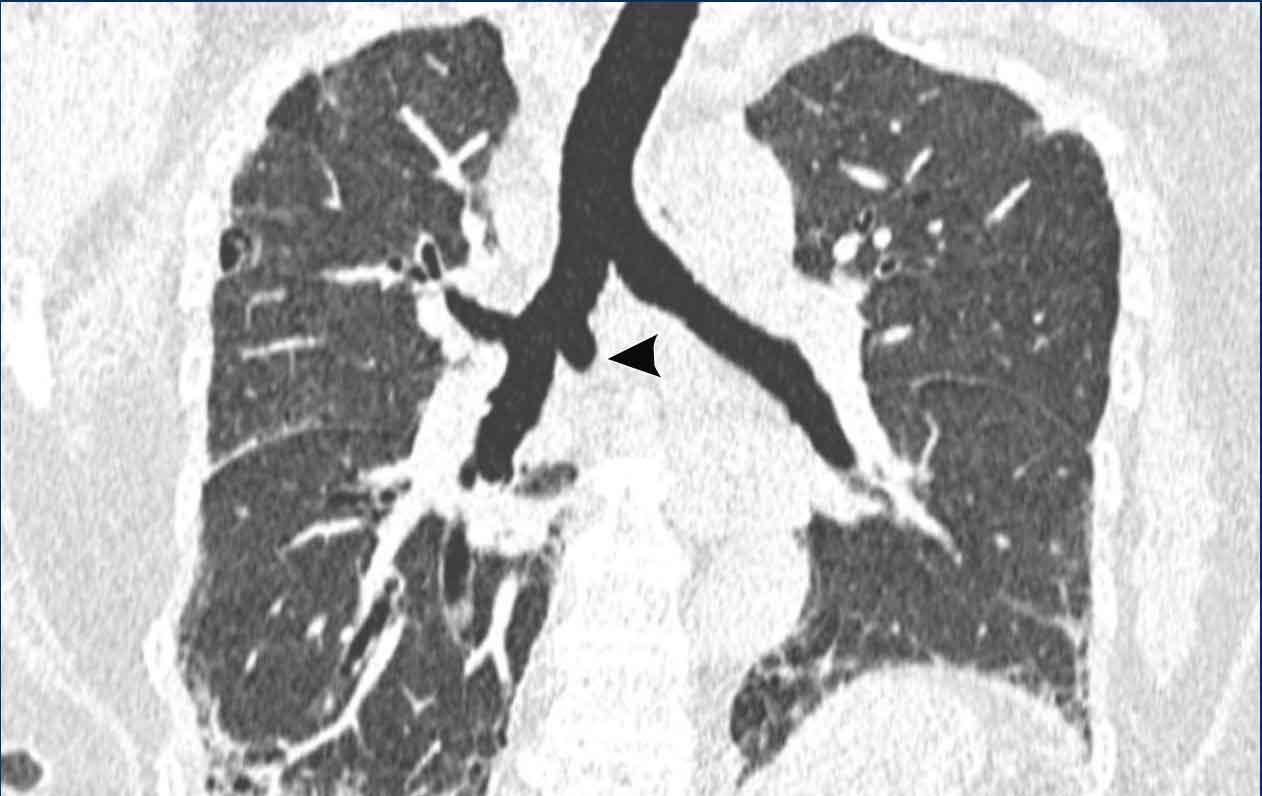

Hình ảnh

Tổn thương đường thở trung tâm trong GPA cho thấy dày thành khí quản theo chu vi ở mức carina ở bệnh nhân nam 43 tuổi. Có xẹp phổi trái do tổn thương mạn tính của phế quản gốc trái gây hẹp lòng.